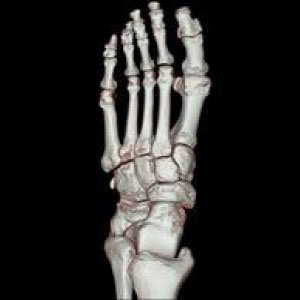

CTとはComputed Tomography(コンピュータ断層撮影)の略です。

検査はエックス線を利用し体の断面を撮影します。頭から全身に至るまで様々な検査が可能です。当院では80列マルチスライスCTを導入し短時間で低被ばくかつ高精細な検査が可能となりました。

脳血管障害、脳腫瘍、頭部外傷、顔面骨骨折、副鼻腔炎、甲状腺疾患、肺炎、肺がん、食道がん、肺塞栓、縦隔疾患、消化管疾患・がん・炎症、泌尿器疾患、婦人科疾患、大動脈瘤、脊椎骨折、骨盤骨折、上下四肢骨折、下肢動静脈疾患など